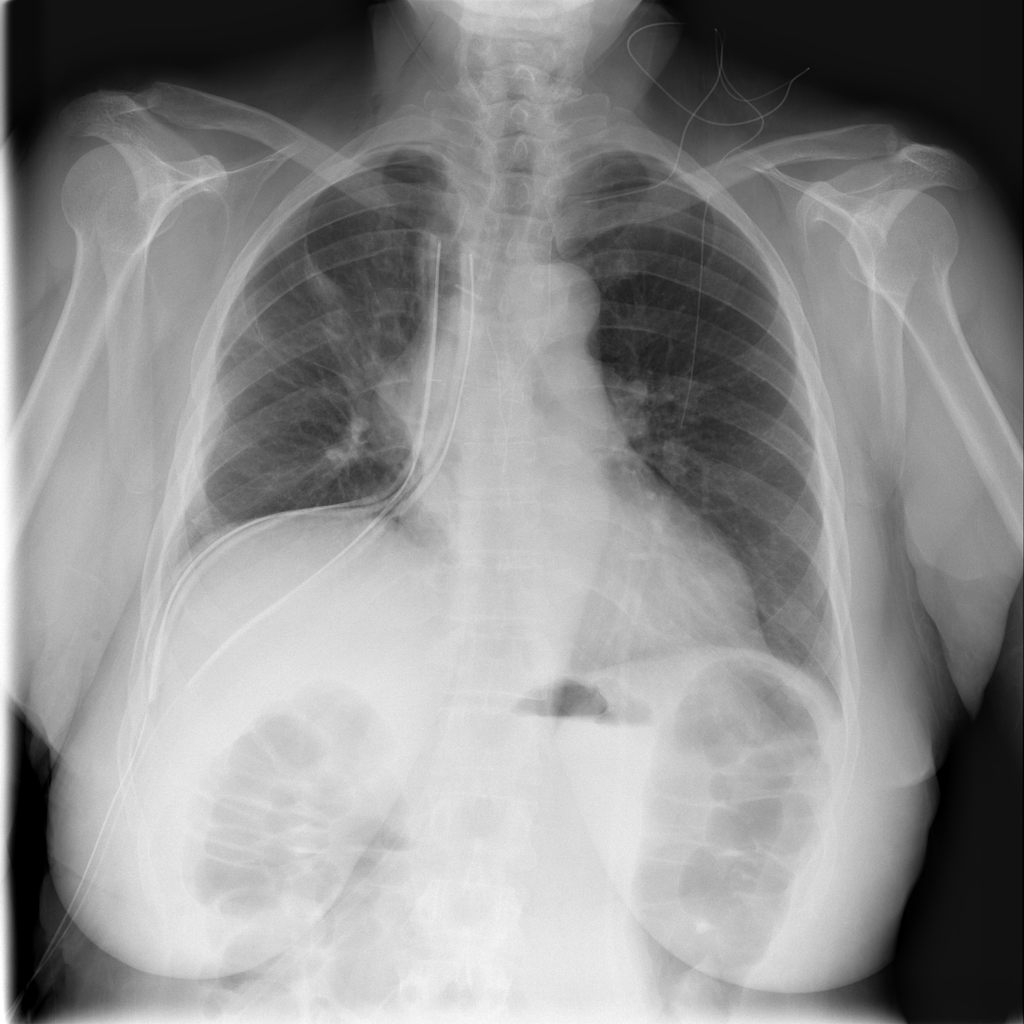

Showing up to 90 reference images for Pneumothorax.

PAT-4639 · IMG-012Pneumothorax

PAT-4639 · IMG-012

AP